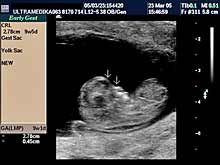

A) I trimestar do 14

nedelje gestacije

(3 meseca + 2 nedelje)

- GENETSKI SONOGRAM (2 - 3 ½ meseca):

- Otkrivanje ultrazvučnih markera na postojanje hromozomskih

anomalija ploda (SKRINING na ANEUPLOIDIJE). Ovaj genetski sonogram

treba uraditi dva puta u intervalu od 9 do 14 nedelje gestacije uz

biohemijsku proveru iz krvi trudnice nakon tačne ultrazvučne procene

veličine ploda. Genetski sonogram sam isključuje oko 88% trizomija,

a udružen sa biohemiskim analizama se isključuje oko 98%

aneuploidija.

- Prva procena i otkrivanje krupnih anatomskih anomalija ploda

koje ne moraju pratiti hromozomske anomalije.

NAPOMENA:

Ultrazvučni markeri za aneuploidije nestaju nakon I

trimestra trudnoće. Nakon toga ove markere nije moguće registrovati.

Blagovremeno otkrivanje dovodi do prekida trudnoće u dozvoljivom

vremenskom terminu. Brojne anatomske anomalije su dostupne otkrivanju

u ovom periodu trudnoće.

Ako su ultrazvučni markeri nedostupni pregledu, genetski sonogram

podrazumeva upotrebu trodimenzionalne tehnike - 3D Sono CT i CPA. |